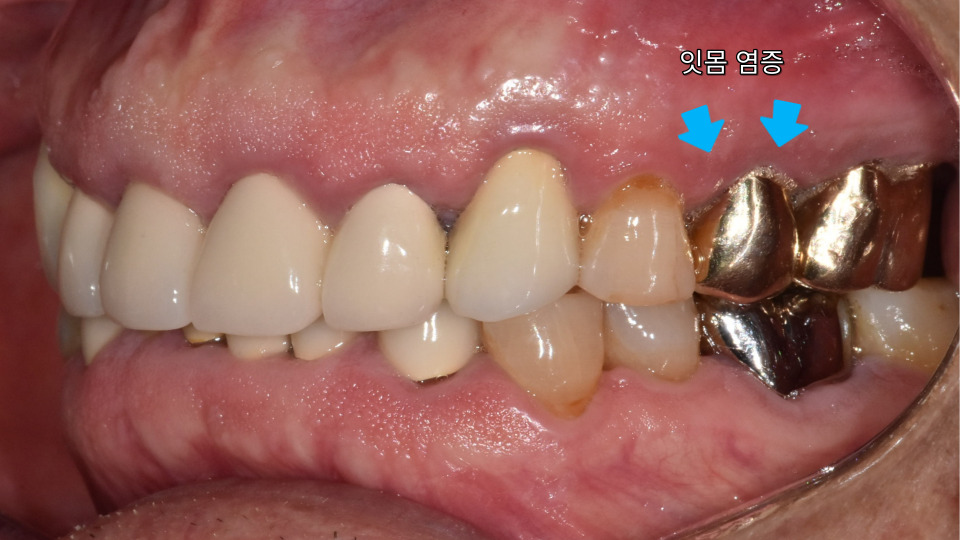

가끔 주변 잇몸이

붓는 느낌이 들긴 했지만

특별히 아프거나 하진

않았다고 하십니다.

잇몸 염증이나 충치처럼

단단한 치아를 상하게 하는

요인이 생겼다면

진단후 새로운 치료가

필요할 수 있는데요.

실제로 잇몸 부근을

측면에서 누르면

살짝 고름이 나오기까지

했는데요.

빠른 시일 내에

발치하는 것이 좋겠습니다.